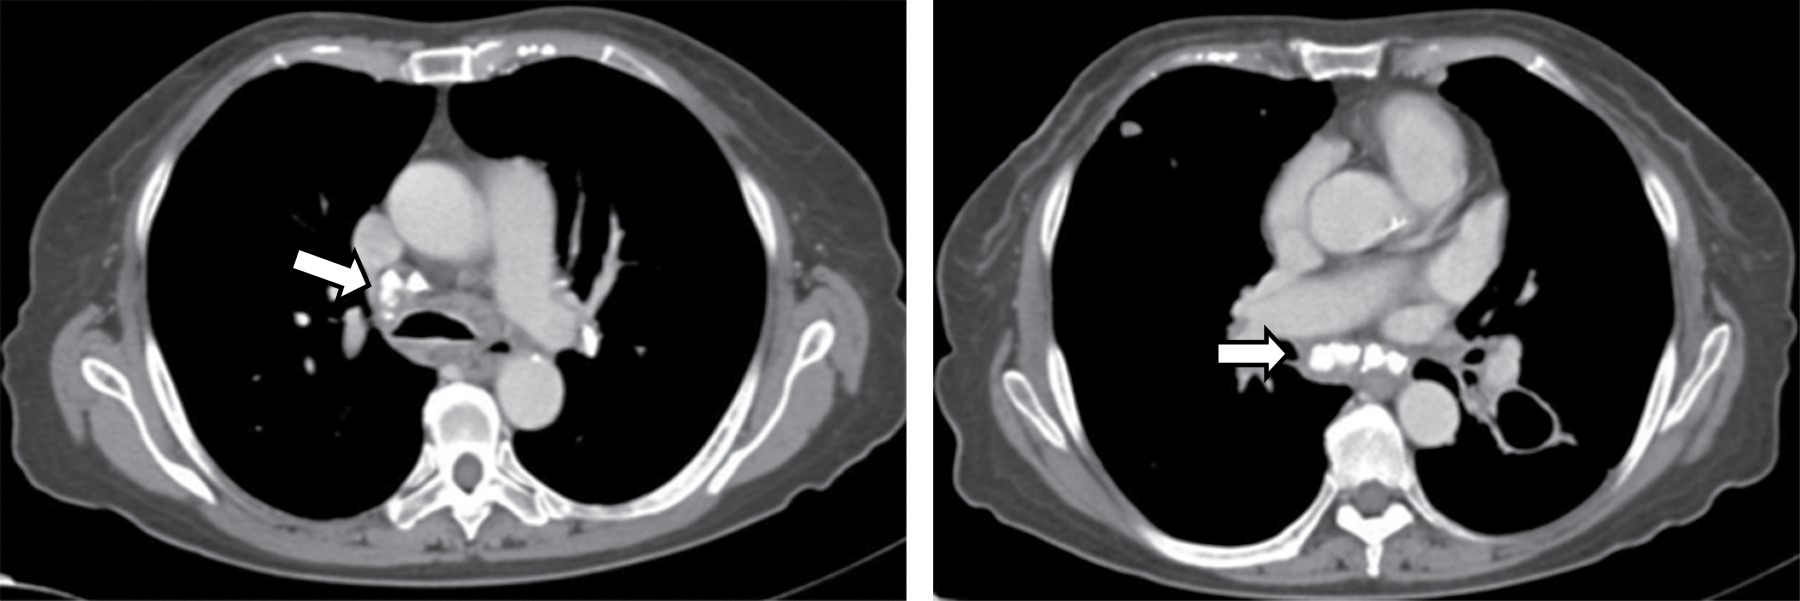

En la TC, típicamente se manifiesta como masas de atenuación de tejidos blandos que obliteran planos grasos mediastinales y encasilla o invade estructuras adyacentes. Sherrik y colaboradores8 identificaron dos patrones de invasión tomográfica: un patrón focal y un patrón difuso. El patrón focal (Figura 3) visto en 82% de los casos, se manifiesta como una masa con atenuación de tejidos blandos que con frecuencia calcifica (63%) y usualmente se localiza en las regiones paratraqueal derecha o subcarinal o en el hilio. El patrón difuso (Figura 4), visto en 18% de los casos como una masa infiltrante no calcificada que afecta múltiples compartimentos mediastinales. El patrón difuso ocurre en el estadio de otros desórdenes fibrosantes idiopáticos tales como fibrosis retroperitoneal.